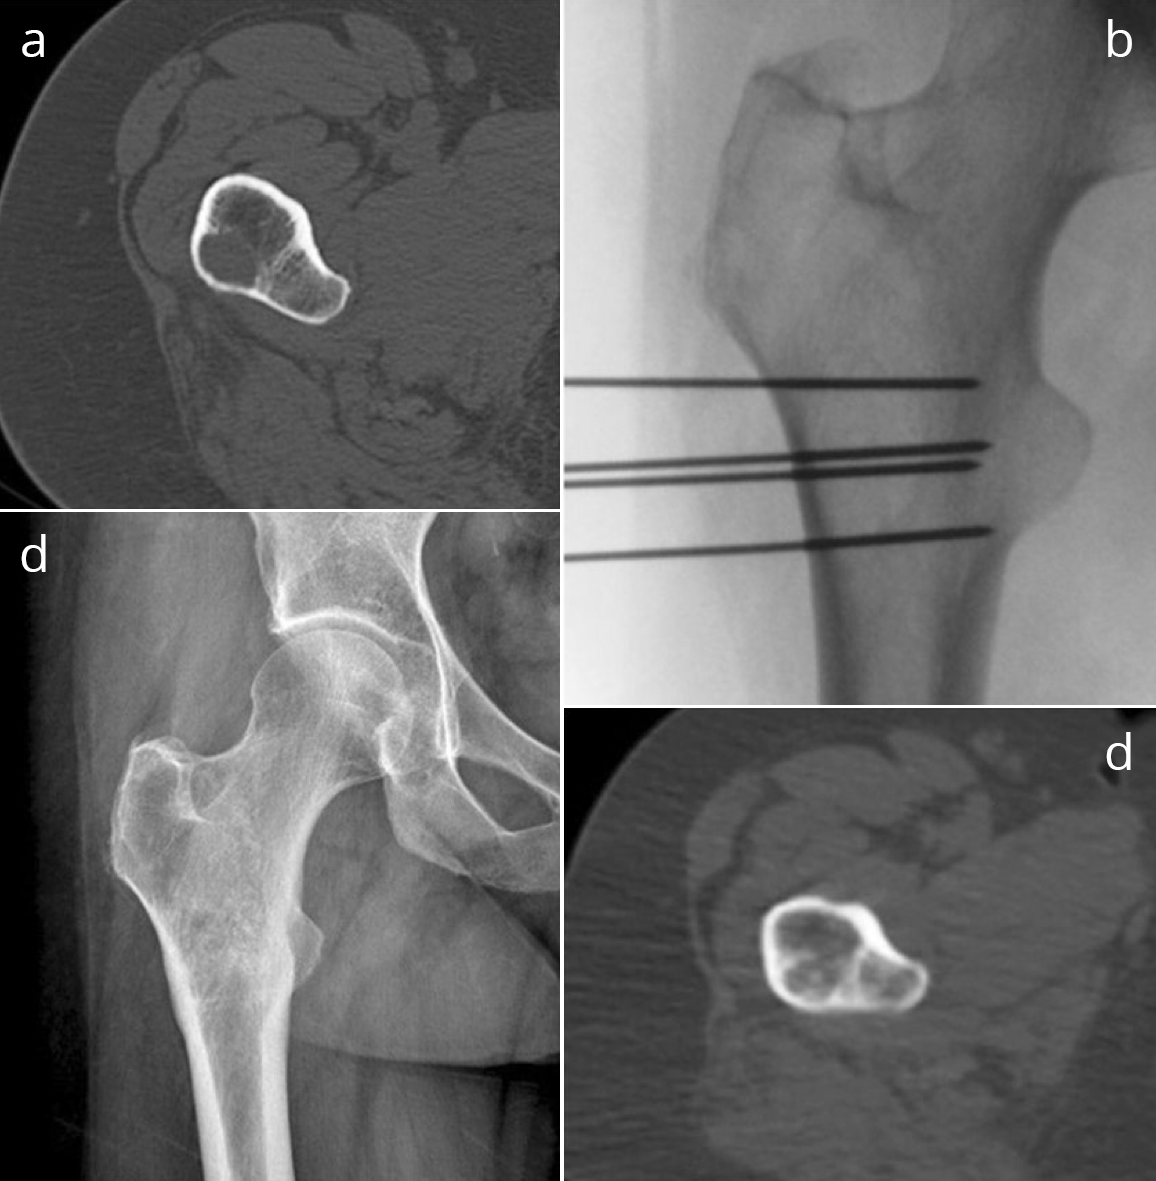

Die Abbildungen zeigten CT und MRT-Scans eines Patienten mit Lymphknotenmetastasen bei einem Prostatakarzinom. Der Patient hatte sich einer Hormonentzugstherapie (ADT Androgen-Deprivations-Therapie) unterzogen, die nicht mehr wirkte. Der PSA-Spiegel war auf 8,65 ng/ml angestiegen. Die Lmyphknotenmetastasen (MRT-Bild rechts oben, Pfeile) sind tief im Becken im Bereich der großen Beckengefäße (Iliakalgefäße) und direkt neben den Ischiasnerven (Nervi ischiadici) lokalisiert. Das Bild rechts oben zeigt die Einbringung der Elektroden in die Lymphknoten im Computertomographen mit Hilfe des infrarotgesteuerten virtual Reality Systems Cascination. Das CT-Bild links unten zeigt die Elektroden in ihrem Verlauf von der Bauchwand bis in die metastasenbefallenen Lymphknoten. Das MRT-Bild rechts unter zeigt das Ergebnis fünf Monate später: Die Lymphknotenmetastasen sind vollständig verschwunden, der PSA-Spiegel sank auf 0,06 ng/ml ab.

Eine sanfte Behandlung von Knochenmetastase ist mit Hilfe der sogenannten Elektro-Chemo-Therapie möglich. Dabei werden, wie bei der IRE, Elektroden in die Knochenmetastasen eingebracht. Anstatt die Zellen durch Stromstöße wie bei der IRE direkt zu zerstören, werden bei der ECT durch sanftere elektrische Pulse Poren in den Zellmembranen erzeugt. Wird gleichzeitig das Zellgift Bleomycin verabreicht, dringt dies vorzugsweise in die durch Elektroporation geöffneten Zellen ein, und tötet diese ab. Zellen außerhalb des Elektroporationsfeldes nehmen das Chemotherapeutikum nur schlecht auf und werden nicht oder nur wenig geschädigt. Die Knochenstruktur wird bei dieser Art der Behandlung von Knochenmetastasen nur wenig bis gar nicht beschädigt. Insbesondere ist eine vollständige Ausheilung des Kochens nach Destruktion der Metastase(n) möglich, was bei einer Strahlentherapie des Knochens nicht der Fall ist.